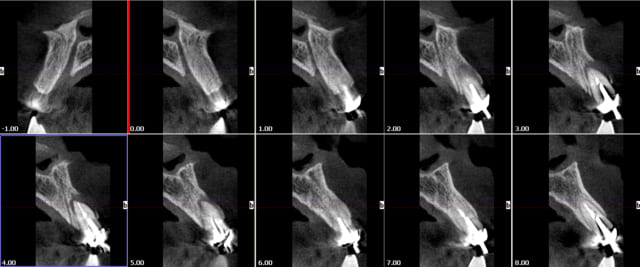

Bon finalement j'ai fait mon choix, cone beam installé hier !

Vatech Ewoo.

Pour moi les plus :

- taille de champ variable: 5*5 8*5 8*8 12.5*8

- vraie combo pano/cone beam

- interface sympa

- artefact métallique limité

- Logiciel d'imagerie et planification implantaire très bien

quelques clichés d'essais

Tu peux mettre une coupe de zone molaire en gros plan pour voir si on voit bien le canal mandibulaire?